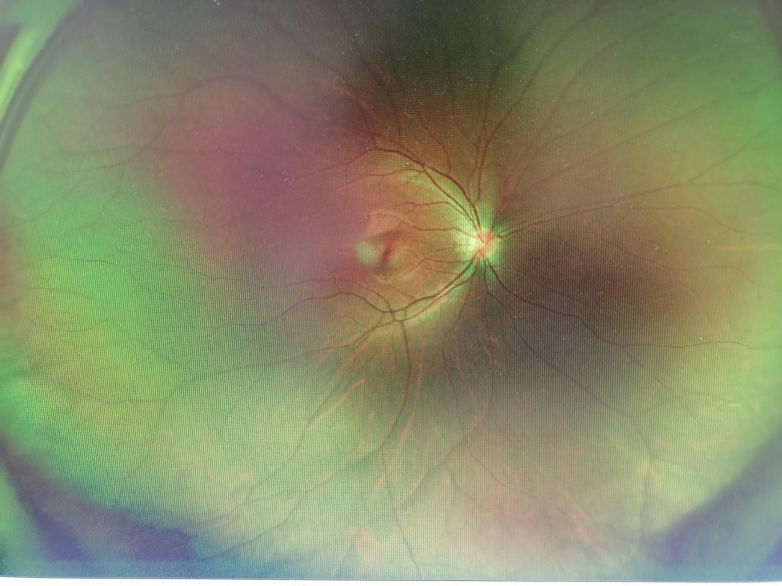

眼底照相检查结果显示,小张左眼颞上方周边部存在视网膜病变。为确保诊疗精准,周医生第一时间将小张转诊至南昌爱尔眼科医院眼底病科会诊,眼底病科赖梦云医生接诊后,立即为小张左眼进行散瞳检查,进一步明确病情。经详细检查发现,小张左眼颞上方玻璃体增殖牵拉视网膜,最终确诊为左眼视网膜变性。为避免眼底病变进一步发展,防止视网膜脱离等严重后果,赖梦云医生建议为小张实施左眼视网膜激光光凝治疗,小张父母听从专业建议,同意接受该治疗。